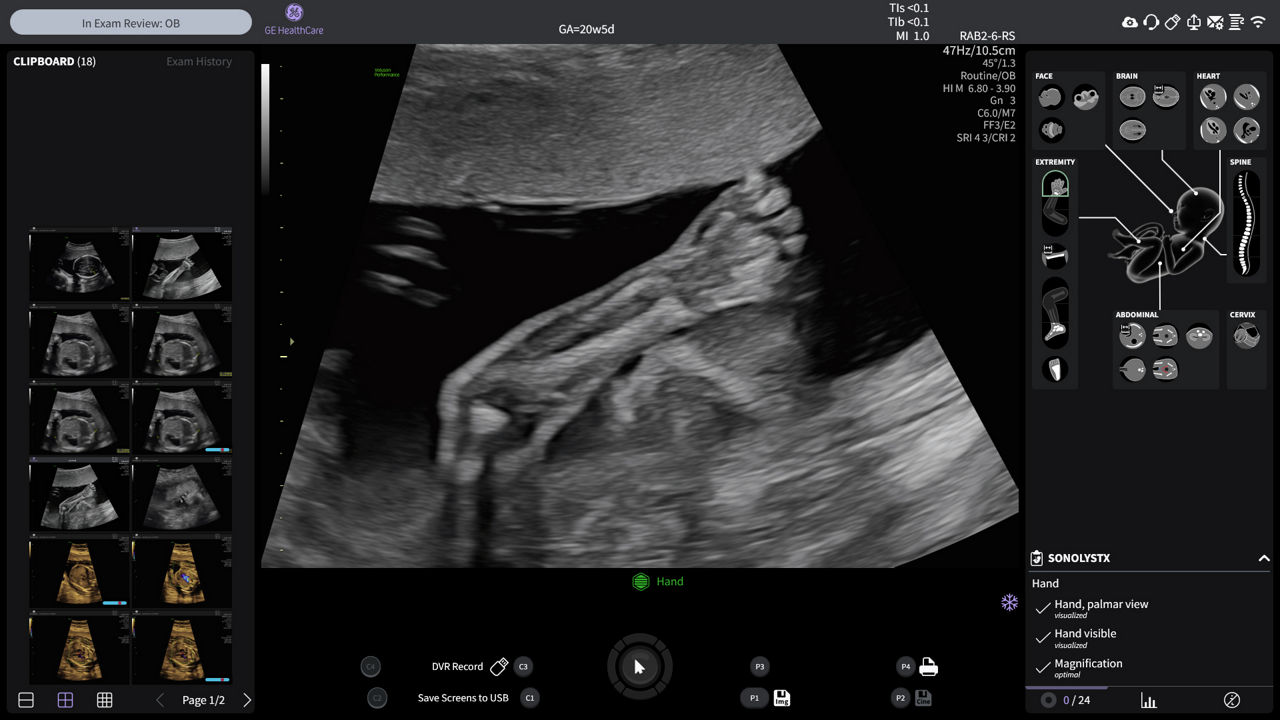

Enhance your workday with leading AI-based technology and progressive tools that simplify and speed up exams. Automate manual tasks and calculations to save time, increase consistency, and improve accuracy.

Routine 2nd tri exam keystrokes reduced by 65% with SonoLyst

Acquire the coronal view of the spine in 1/2 the time using Spine Trace.